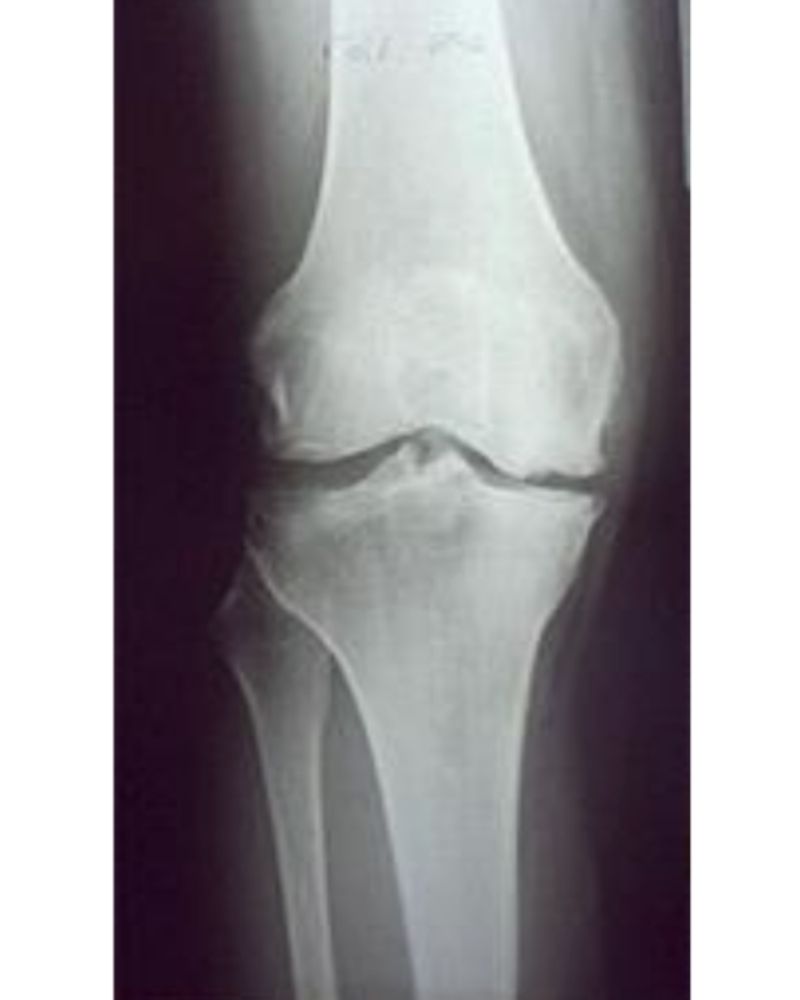

Rx Preoperatoria

Rx postoperatoria

L’artrosi del ginocchio (gonartrosi) può manifestarsi con usura della cartilagine associata alla formazione di osteofiti (per iperproduzione di osso ai margini articolari) e riassorbimento dell’osso subcondrale con formazione di geodi.

Nel tempo, tutti questi fenomeni portano a una progressiva deformazione dell’articolazione con limitazioni della sua funzionalità tali da compromettere la mobilità e la qualità di vita.